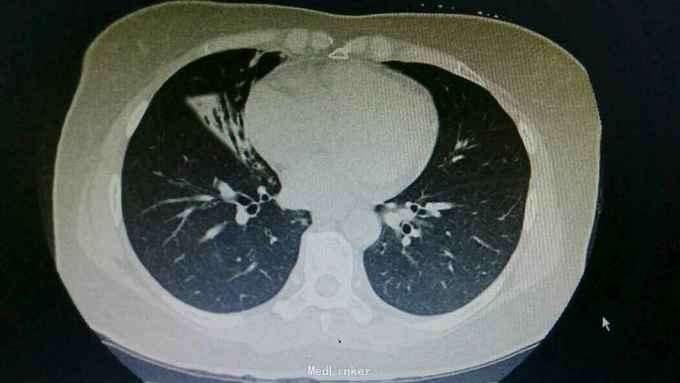

主诉:咳嗽8天,咯血6天。 病史:患者自诉8天前无明显诱因出现咳嗽,为刺激性干咳,未予以处理,6天前出现咯血,具体量不祥,为求诊治,入住我科。

查体:右下肺闻及湿性啰音,余无特殊。 辅查:胸部CT:右肺中上叶支扩并感染,双肺下叶磨玻璃影,考虑肺泡内积血可能。

诊断:支扩并咯血。 治疗:入院予以抗感染,止血,止咳化痰等治疗。